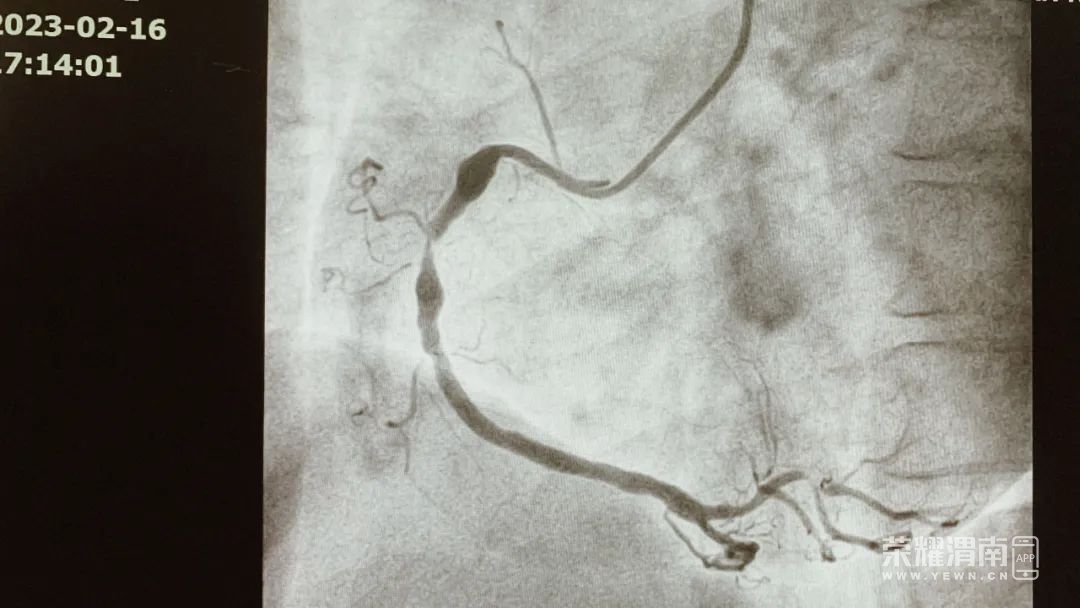

患者 63岁

急性心肌梗死入住

心脏中心监护病房

治疗过程中出现

室速室颤随即发生心脏骤停

医护反应及时

紧急启动应急措施

通过除颤用药

急诊手术后患者转危为安

恢复良好